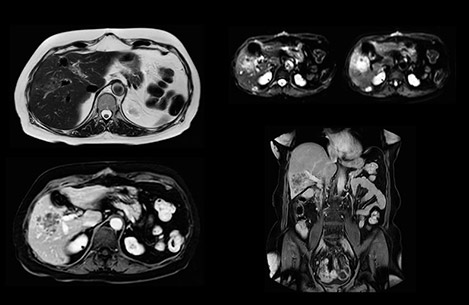

Comparison of liver MRI with and without MultiVane XD motion correction

In this example the image quality of the MultiVane XD images is evidently better than in the images without MultiVane XD. Ingenia 1.5T with dS Torso coil solution.